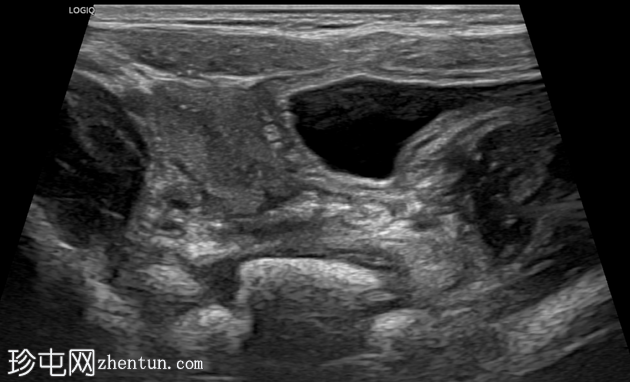

横切面

右侧努克氏疝管长约6毫米,内含部分子宫和卵巢(大小约1.5 x 1厘米)。在整个检查过程中,这些组织均保持原位。

上述超声特征清晰地显示了努克氏疝管的内容物及其延伸范围;其中包含患者的一侧卵巢和部分子宫组织。

这些特征符合卵巢努克氏疝的诊断。